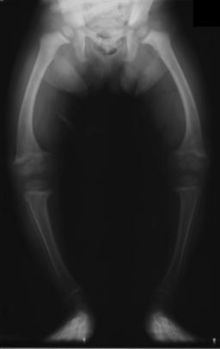

Radiograph of a rickets sufferer

Primidone, along with phenytoin and phenobarbital, is one of the anticonvulsants most heavily associated with bone diseases such as osteoporosis, osteopenia (which can precede osteoporosis), osteomalacia and fractures.[29][30][31] The populations usually said to be most at risk are institutionalized people, postmenopausal women, older men, people taking more than one anticonvulsant, and children, who are also at risk of rickets.[29] However, it has been suggested that bone demineralization is most pronounced in young people (25–44 years of age)[30] and one 1987 study of institutionalized people found that the rate of osteomalacia in the ones taking anticonvulsants—one out of nineteen individuals taking an anticonvulsant (vs. none among the thirty-seven people taking none) —was similar to that expected in elderly people. The authors speculated that this was due to improvements in diet, sun exposure and exercise in response to earlier findings, and/or that this was because it was sunnier in London than in the Northern European countries which had earlier reported this effect.[31] In any case, the use of more than one anticonvulsant has been associated with an increased prevalence of bone disease in institutionalized epilepsy patients versus institutionalized people who did not have epilepsy. Likewise, postmenopausal women taking anticonvulsants have a greater risk of fracture than their drug-naive counterparts.[29]

Anticonvulsants affect the bones in many ways. They cause hypophosphatemia, hypocalcemia, low Vitamin D levels, and increased parathyroid hormone. Anticonvulsants also contribute to the increased rate of fractures by causing somnolence, ataxia, and tremor which would cause gait disturbance, further increasing the risk of fractures on top of the increase due to seizures and the restrictions on activity placed on epileptic people.Increased fracture rate has also been reported for carbamazepine, valproate and clonazepam. The risk of fractures is higher for people taking enzyme-inducing anticonvulsants than for people taking non-enzyme-inducing anticonvulsants.[30] In addition to all of the above, primidone can cause arthralgia.[22]